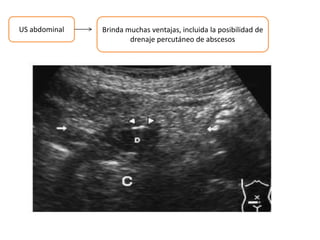

US abdominal Brinda muchas ventajas, incluida la posibilidad de

drenaje percutáneo de abscesos